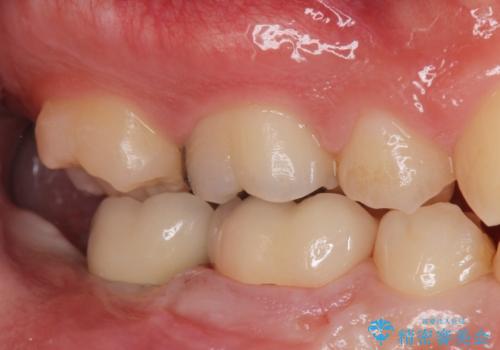

- 銀歯を白くしたいとのことで来院。

右下の被せ物を外し虫歯を除去したところ虫歯が深く保存が難しい状態だったので抜歯を行いました。

手前の銀の詰め物のところは除去して拡大鏡下で虫歯を取り除き、ジルコニアクラウンで治療を行いました。